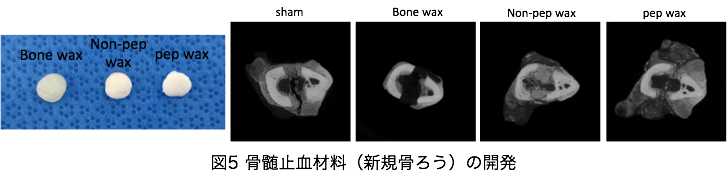

ii) 骨再生を促進する骨髄止血材料(新規骨ろう)の開発

手術等で骨を切開した場合、骨髄からの出血を制御しないと、失血し術野の操作に支障をきたす。この制御にはミツロウ(骨ろう)が使用されてきたが、感染を惹起したり、骨折治癒を抑制することがある。我々は、生体吸収性ポリマーにペプチドを配合し、ミツロウ同等の物性で、骨再生を促す材料を、他施設との共同研究で成功した。